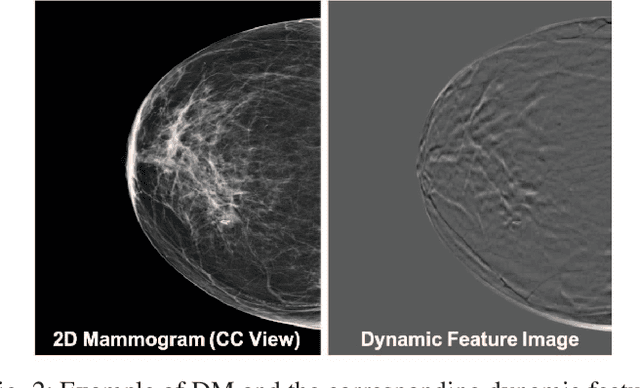

Abstract:Breast cancer is the malignant tumor that causes the highest number of cancer deaths in females. Digital mammograms (DM or 2D mammogram) and digital breast tomosynthesis (DBT or 3D mammogram) are the two types of mammography imagery that are used in clinical practice for breast cancer detection and diagnosis. Radiologists usually read both imaging modalities in combination; however, existing computer-aided diagnosis tools are designed using only one imaging modality. Inspired by clinical practice, we propose an innovative convolutional neural network (CNN) architecture for breast cancer classification, which uses both 2D and 3D mammograms, simultaneously. Our experiment shows that the proposed method significantly improves the performance of breast cancer classification. By assembling three CNN classifiers, the proposed model achieves 0.97 AUC, which is 34.72% higher than the methods using only one imaging modality.

Abstract:Automated methods for breast cancer detection have focused on 2D mammography and have largely ignored 3D digital breast tomosynthesis (DBT), which is frequently used in clinical practice. The two key challenges in developing automated methods for DBT classification are handling the variable number of slices and retaining slice-to-slice changes. We propose a novel deep 2D convolutional neural network (CNN) architecture for DBT classification that simultaneously overcomes both challenges. Our approach operates on the full volume, regardless of the number of slices, and allows the use of pre-trained 2D CNNs for feature extraction, which is important given the limited amount of annotated training data. In an extensive evaluation on a real-world clinical dataset, our approach achieves 0.854 auROC, which is 28.80% higher than approaches based on 3D CNNs. We also find that these improvements are stable across a range of model configurations.